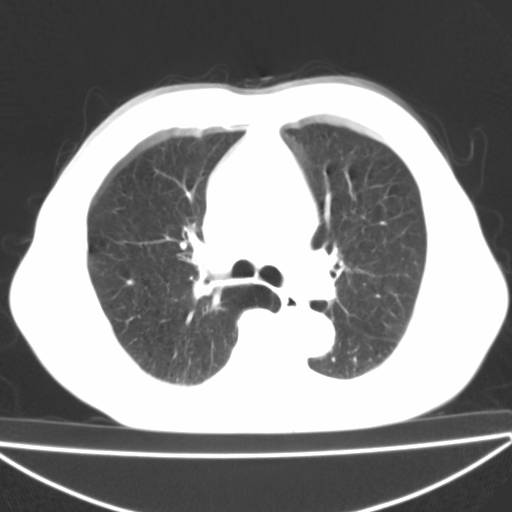

以下是引用zjzjr在2006-12-6 19:04:00的发言:[br]左肺上叶尖后段可见椭圆形高密度影,其内可见点状钙化影,周围可见卫星病灶.首先考虑结核,双侧少量胸腔积液.

以下是引用李世军在2006-12-6 19:54:00的发言:[br]左肺上叶尖后段可见椭圆形高密度影,其内可见点状钙化影,周围可见卫星病灶.首先考虑结核,双侧少量胸腔积液. [br] [br] 双肺轻度肺气肿,左肺上叶后段见多发斑片状密度增高影,周围见少许斑点状卫星病灶,双侧胸膜增厚粘连,纵隔内未见明显改变,考虑结核可能性大,请结合临床或增强扫描. [br] [br]

以下是引用13081830109在2006-12-6 19:35:00的发言:[br]左肺上叶尖后段可见椭圆形高密度影,其内可见点状钙化影,周围可见卫星病灶.首先考虑结核,双侧少量胸腔积液.